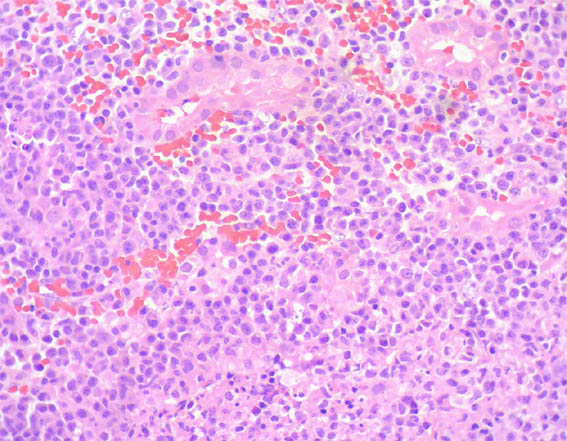

An allograft kidney biopsy was done. See the images.

Figure 2. H&E, X200.